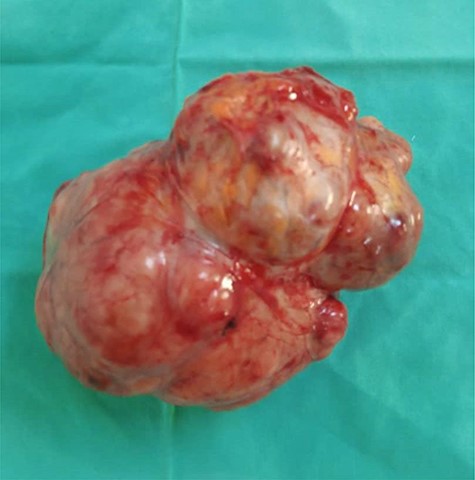

A 54-year-old female was admitted with a 6-month history of a painless abdominal mass, gradually increasing in size. She was a lifelong teacher in secondary school and has lived in one area for a lifetime, there was no asbestos-related facility. She had never been exposed to asbestos and had received an appendectomy and caesarean section, respectively, 8 and 15 years ago. She was not smoking, and her family history was negative for malignancy. On admission, she looked in a good health state, her vital signs were stable, and a movable and painless intracavitary mass was palpable over the right side of the abdomen, but ascites signs were absent. The blood count showed a white cells count of 13.100/mm3 (neutrophils 70.2%, lymphocytes 39.6%), haemoglobin of 12.4 g/dl, and platelets count of 200.000/mm3. The blood chemistry showed a creatinine level of 10 mg/l, urea 0.11 g/l and CRP < 6 mg/dl. As a result of the abdominal computed tomography scan was not sufficiently conclusive on the nature of the mass, the surgical team decided to perform an exploratory laparotomy. Laparotomy showed a localized mesenteric encapsulated and firm tissue mass weighing ~500 grams and measuring 12.5 × 10.5 × 8 cm, with no evidence of inflammation, mesenteric lymph nodes and ascites (Fig. 1). Microscopically, the tumor consisted of moderately polymorphic spindle-shaped neoplastic cells with elongated moderately pleomorphic hyperchromatic nuclei, with low mitotic activity and infiltrating connective tissue (Fig. 2). These histopathological features were compatible with a low grade sarcomatoid malignant mesothelioma. The neoplasic cells were positive with keratin AE1/AE3, CAM 5.2, and negative for desmin and CD34, which was consistent with the diagnosis. The patient has been referred to oncologist, and adjuvant chemotherapy protocol has been planned.

Well defined lobulated and encapsulated mass weighing ~500 g and measuring 12.5 × 10.5 × 8 cm dimensions.

In many reported cases, malignant peritoneal mesothelioma appeared at laparotomy as a widespread nodular thickening of the visceral peritoneum with a striking, diffusely uniform, erythematous appearance or omental cake with peritoneal nodular seed with the presence of ascites [1, 4, 7]. In our case, it was different with a gross appearance of a localized mesenteric encapsulated tissue mass weighing ~500 g and measuring 12.5 × 10.5 × 8 cm, with no inflammation, mesenteric lymph nodes and ascites. Note that localized form of malignant peritoneal mesothelioma is very rare, representing about 2% of macroscopic presentations of this neoplasm [6]. In the case reported by Saisho et al. [6] of localized biphasic malignant mesothelioma presenting as a rectal tumor, the neoplasm measured 8 cm of maximal diameter, which is comparable in size to the mesenteric tumor of our patient.